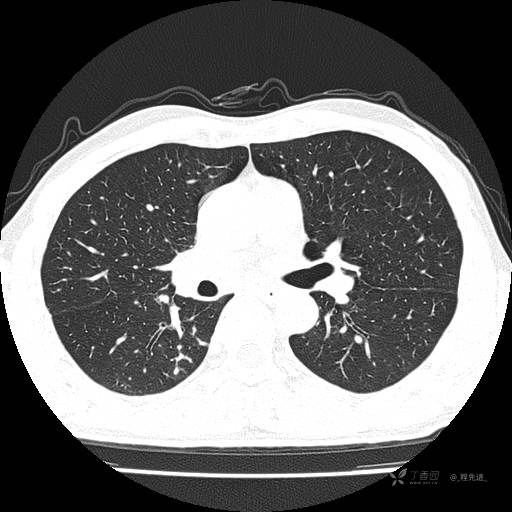

2月特别精彩病例|咳嗽、咳痰20余天,典型病例分享【结果已公布】

患者年龄:51岁

主诉:咳嗽、咳痰20余天

简要病史:20余天前开始出现咳嗽、咳痰症状,阵发性刺激性咳,白色粘痰,不易咳出,无发热,无咯血,无恶心、呕吐等不适,未诊治,咳嗽、咳痰症状持续存在。

体格检查:T:36.3 ℃ P:79 次/分 R:20 次/分 BP:128/64 mmHg,神志清楚,呼吸平稳,双肺呼吸音粗,右下肺闻及细湿性啰音。心率79次/分,节律整齐,各瓣膜听诊区未闻及病理性杂音。腹部未见异常,双下肢无水肿。

辅助检查:我院门诊胸部CT示:如下。心电图:窦性心律;正常心电图。